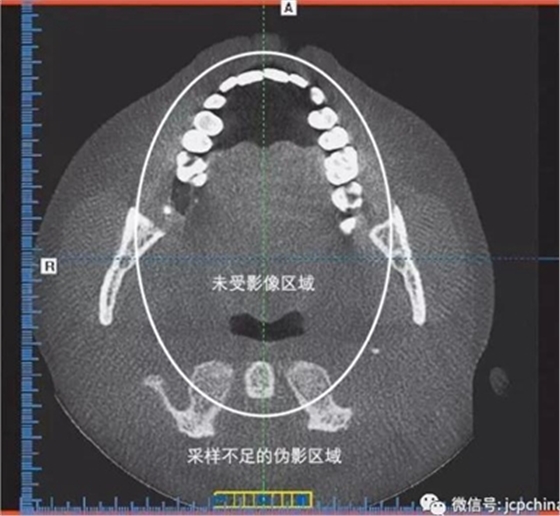

(4)混淆偽影

X線束為錐形的和發(fā)散的,不難看出離放射源最遠(yuǎn)的那部分采樣量不足。采樣不足的偽影顯示為彎曲的紡錘線。偽影在圖像周邊比較明顯,而中央?yún)^(qū)域未受影響。